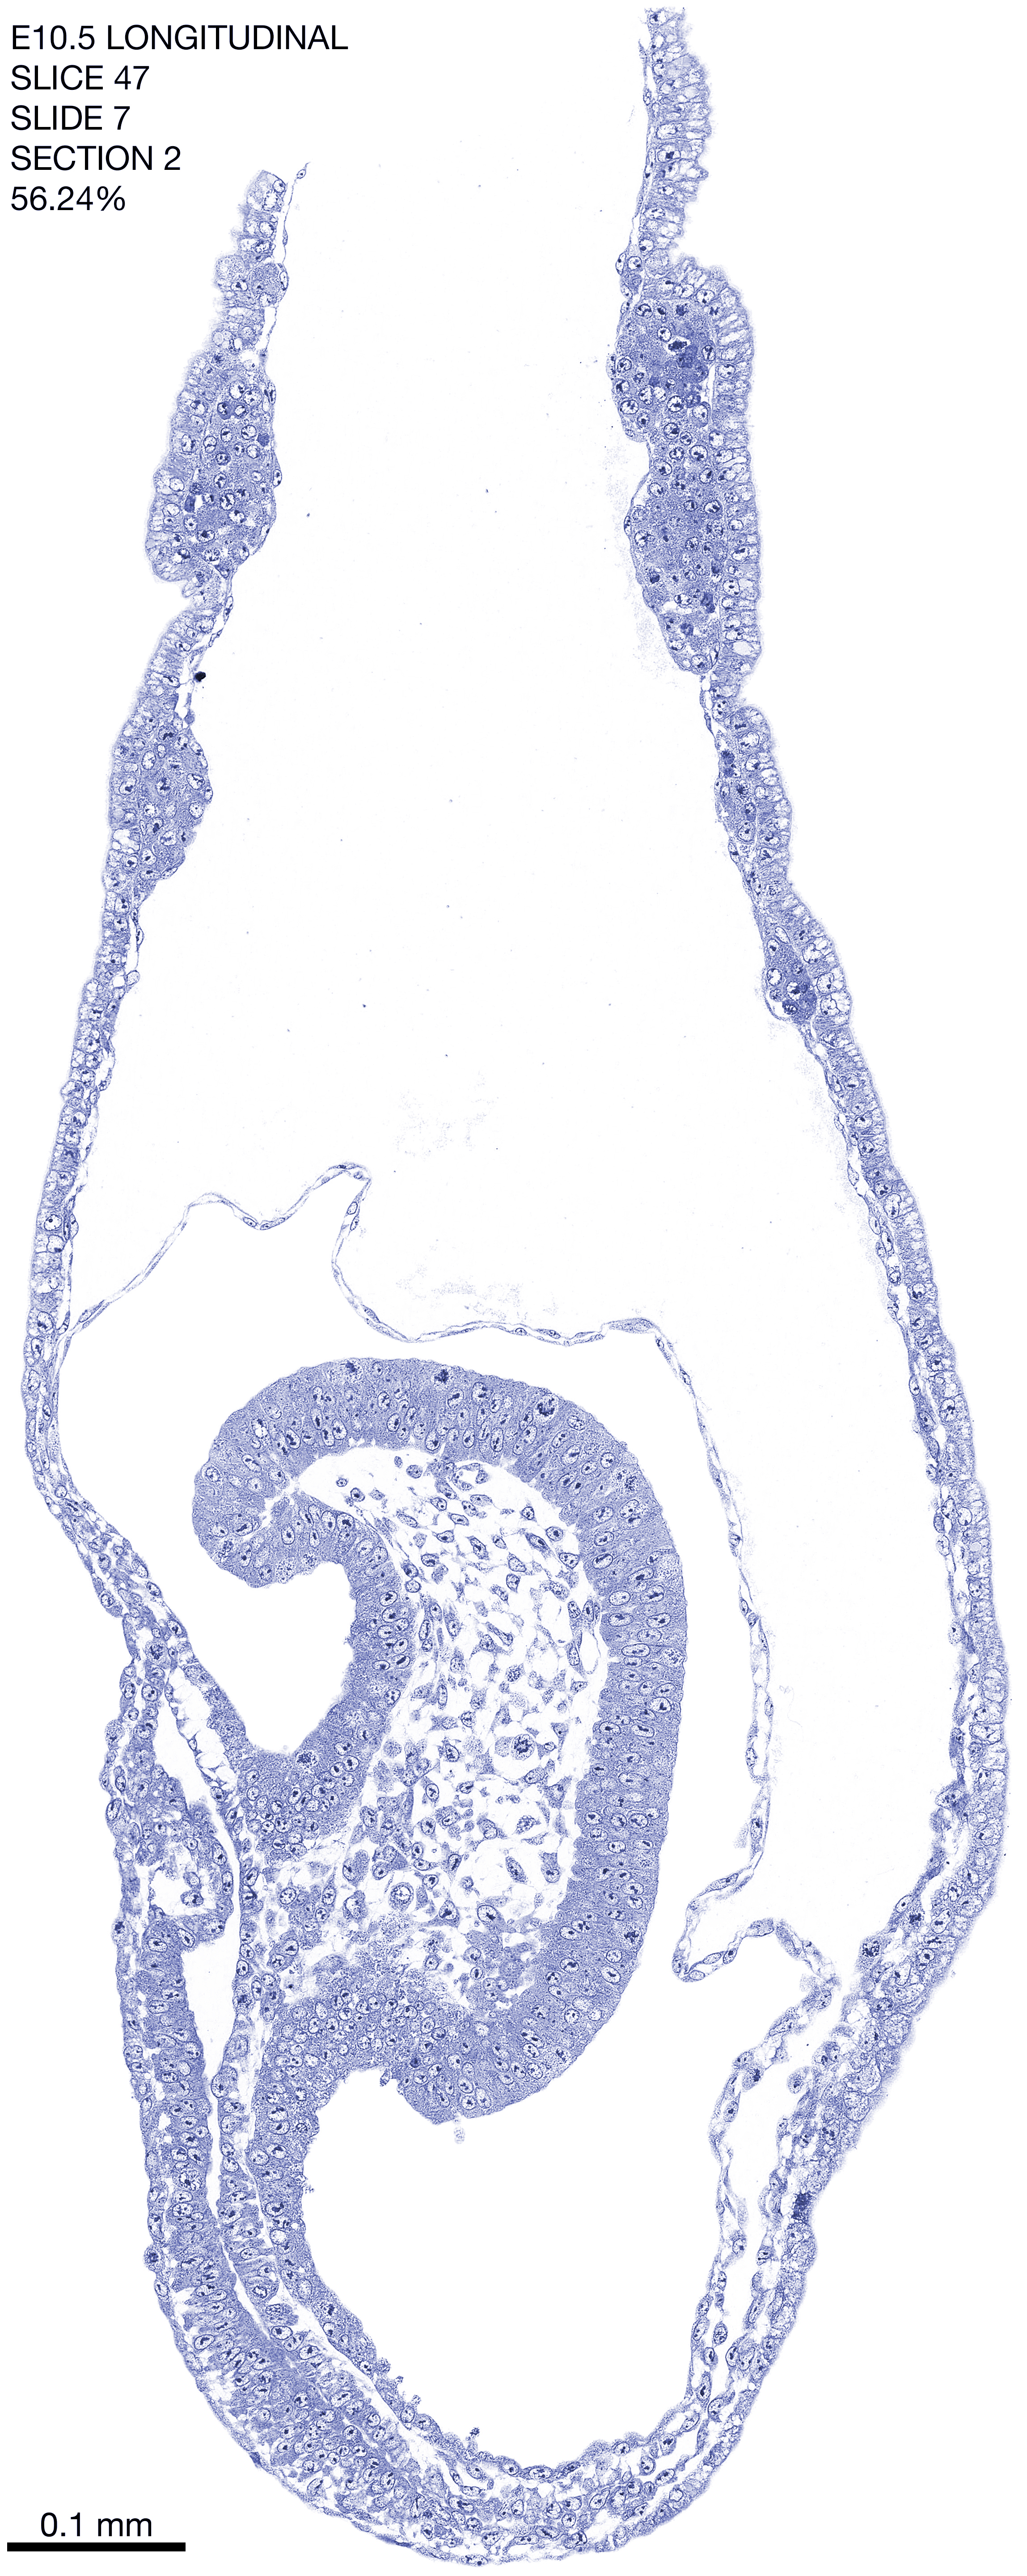

E10.5 Longitudianal Archive This page contains jpg files of ALL SLICES (each 3µm thick) that were scanned of the E10.5 longitudinally cut specimen. Download: Large | High Res Download: Large | High Res Download: Large | High Res Download: Large | High Res Download: Large | High Res Download: Large | High Res Download: Large | High Res Download: Large | High Res Download: Large | High Res Download: Large | High Res Download: Large | High Res Download: Large | High Res Download: Large | High Res Download: Large | High Res Download: Large | High Res Download: Large | High Res Download: Large | High Res Download: Large | High Res Download: Large | High Res Download: Large | High Res Download: Large | High Res Download: Large | High Res Download: Large | High Res Download: Large | High Res Download: Large | High Res Download: Large | High Res Download: Large | High Res Download: Large | High Res Download: Large | High Res Download: Large | High Res Download: Large | High Res Download: Large | High Res Download: Large | High Res Download: Large | High Res Download: Large | High Res Download: Large | High Res Download: Large | High Res Download: Large | High Res Download: Large | High Res Download: Large | High Res Download: Large | High Res Download: Large | High Res Download: Large | High Res Download: Large | High Res Download: Large | High Res Download: Large | High Res Download: Large | High Res Download: Large | High Res Download: Large | High Res Download: Large | High Res Download: Large | High Res Download: Large | High Res Download: Large | High Res Download: Large | High Res Download: Large | High Res Download: Large | High Res Download: Large | High Res Download: Large | High Res